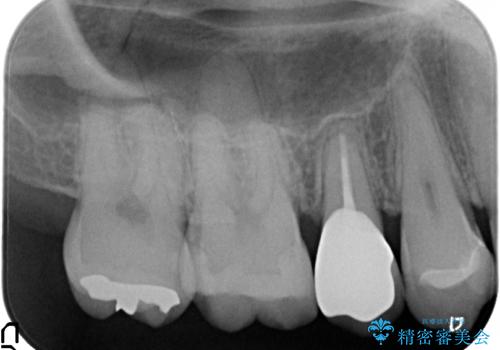

治療途中

終了時